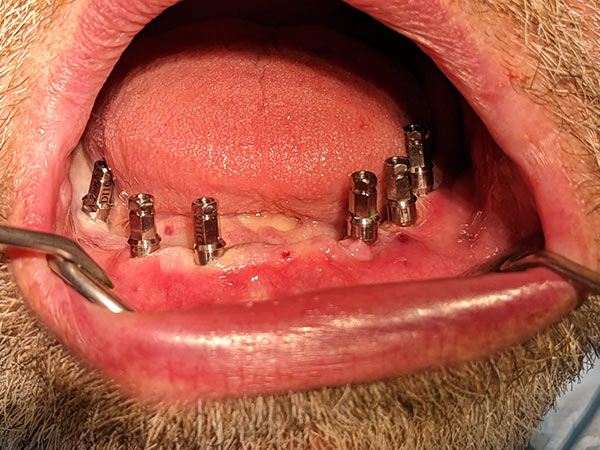

Sono state eseguite Tac con dima radiologica e progettazione per inserimento implantare tramite dima chirurgica di sei impianti AZ Implant tipo DX con overdenture a carico immediato.

L’intervento è stato eseguito dal Dr. Matteo Pini con dispositivi medici AZ Implant.